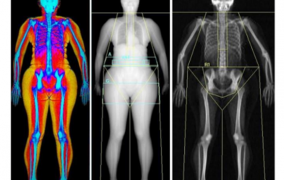

The new functionalities allow the Cancer Theranostics Innovation Center to generate dynamic, more detailed images and provide more accurate diagnoses. The device is available to the scientific community in the state of São Paulo.